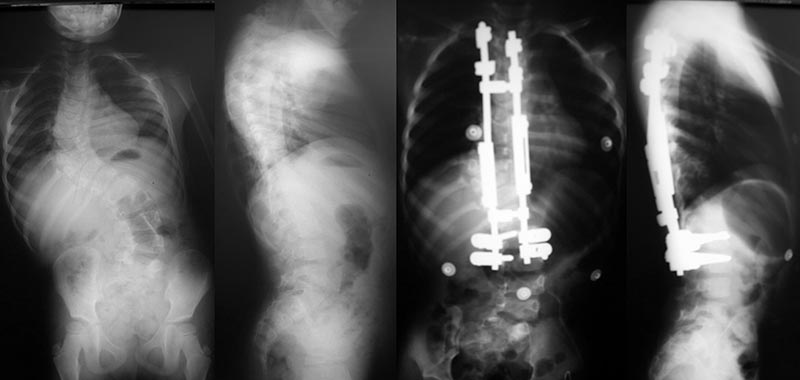

- Instrumentação sem fusão: Hastes de crescimento (Growing Rods – exemplo figura 8): criança em crescimento, curvas longas e flexíveis, necessidade de cirurgias frequentes para distração, problemas com anestesia frequente em crianças com cérebro em desenvolvimento. VEPTER: indicação: menores de 6 anos, tórax assimétrico, fusão ou ausência de costelas (exemplo figura 9).

Figura 8. Tutores de crescimento por distração (Growing Rods).